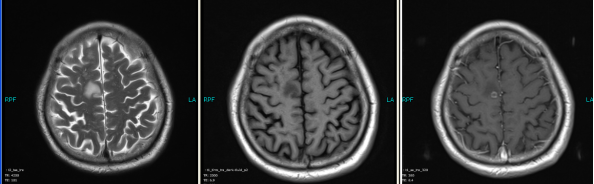

A 66-year old male patient with a smoking history was received by the Outpatient Department on September 14, 2015 due to “coughing for more than one month”. Main symptoms included a dry cough, a small amount of white phlegm, but freedom from fever, chest pains, bloody sputum, and any other discomfort. Stage IV-lung cancer is associated with anorexia and a loss of nearly 10 pounds. The patient had a poor constitution in the past, with a history of “acute hepatitis”, “type-2 diabetes” and “obsolete pulmonary tuberculosis”. The patient was accepted in the Department of Respiratory Medicine on September 15. The results of a lung CT scan indicated a “space occupied for posterior basal segment of right inferior lung and enlarged for mediastinal lymph nodes”. The patient was approved for a CT- guided transthoracic needle biopsy, immunohistochemistry, EGFR gene mutation detection, and systemic metastases assessment. He was diagnosed as “primary lung cancer, right lung adenocarcinoma, T4N3M1B (lung, pleura and brain), and stage-IV EGFR Exon 19 deletion mutation (Fig. 1A and Fig. 2A)”.

The patient checked for further treatment on November 23, 2015. A pre-chemotherapy assessment was made and the results showed multiple bone metastases and multiple enlarged lymph nodes in the left shoulder blade, the fourth lumbar, the right iliac bone and other locations. Performance status (PS) was only one point. Pemetrexed Disodium (500 mg/m2 d1) + Carboplatin (AUC 5 d1) + Bevacizumab (7.5 mg/Kg d1) was administered beginning November 26, 2015 for the chemotherapy treatment and supportive therapy was provided, such as, dehydration, reduction of intracranial pressure, promotion of bone repair, pain relief, and waist protection. After discharge, the coughing basically disappeared and the dizziness, backaches, and hemiparesthesia of the left side were significantly improved. Patient emotional state and sleep quality was significantly improved. It was basically normal after a routine blood examination. A second chemotherapy treatment was successfully completed on December 18 (the program is idem). The patient returned to the hospital on January 6, 2016 and was proposed for a third chemotherapy. The pre-chemotherapy assessment showed that the measurable, targeted right lung lesion had decreased (3.2 mm, with a rate of decrease 44.8 %) (Fig. 1D). Lymphangitis carcinomatosa was significantly decreased and right frontal nodulus lesions were reduced significantly (Fig. 2C). No new lesions were found. Efficacy was assessed as partial relief (PR). A third and fourth chemotherapies were completed on January 9 and January 30, 2016. Efficacy was re-assessed as PR (Fig. 1E) with lung CT review as an outpatient on February 11. Since then, the patient had been subjected to a combined administration program of pemetrexed disodium (500 mg/m2 d1) + bevacizumab (7.5 mg/Kg d1) for continued chemotherapy. A lung CT and a cranial MRI were peformed on April 16. The results showed that the control of lung lesions and intracranial lesions were basically the same as before (Fig.1F and Fig. 2D). The patient had no cough, backaches, or hemiparesthesia and the quality life significantly improved. PS was decreased to zero.